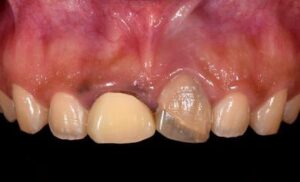

前歯2本のインプラントを用いた審美用例

前歯2本のインプラントを用いた審美用例 BEFORE AFTER 23歳女性/上1本欠損/インプラント埋込手術 【治療内…